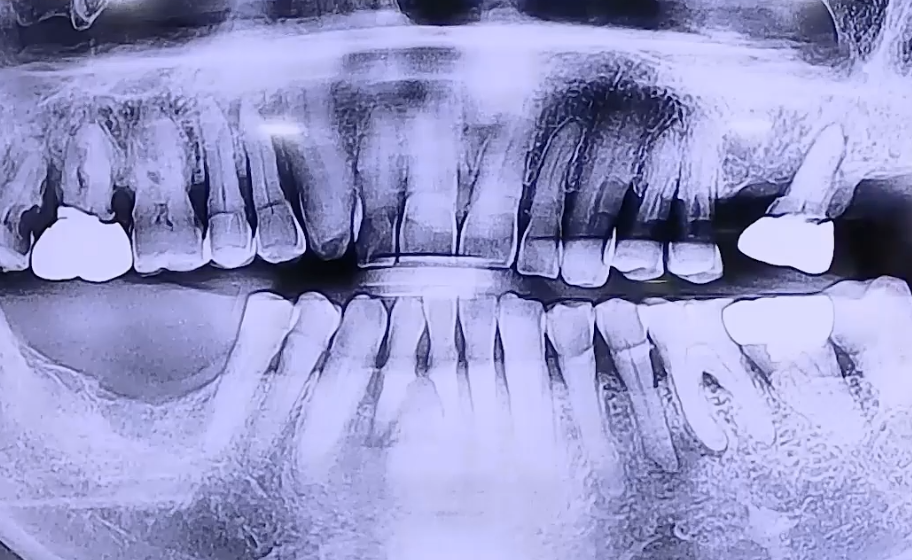

아래 앞니의 통증을 호소하며 내원해 주셨던 환자분이십니다.

통증을 느끼는 쪽 치아가 흔들리고 계셨고, 오른쪽 아래 어금니가

예전에 발치하셔서 없으며 왼쪽은 위 어금니가 하나만 남아있었는데요.

오른쪽 아래 어금니가 없기 때문에 오랫동안 왼쪽으로 식사하신 영향으로

왼쪽 치아 상태도 점점 약해지면서 앞니 쪽으로 식사를 하게 되셨던 것으로 확인되었습니다.

좌우 골고루 치아를 사용하실 수 있도록 오른쪽 아래 어금니, 왼쪽 위 어금니에

임플란트 치료를 진행하시고, 약해졌던 앞니도 얇은 임플란트로 치료해 드렸습니다.